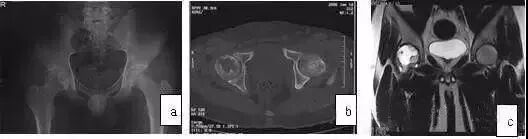

发生在髋关节的PVNS较膝关节少得多,患者多为青少年,常为单发,髋部中、轻度疼痛伴明显关节功能障碍,X线摄片可见股骨头、颈及髋臼皮质骨侵袭,囊性变,关节间隙变窄,此与ONFH不同,后者早、中期时关节间隙不变窄。

应用MRI检查,则鉴别不难。MRI示广泛滑膜病变(T1WI、T2WI均为低信号),病变侵犯广泛(股骨头颈、髋臼)是其特点,CT扫描可见骨皮质侵蚀,累及髋臼和股骨头、颈部,与ONFH鉴别不难(图10)。

图10 男,28岁,右髋钝痛二年,关节活动明显受限,诊断为色素沉着绒毛结节滑膜炎。(a)MRI的T1WI示右股骨头、颈弥散性低信号;(b)X线片示右髋股骨头及髋臼破坏,关节间隙变窄;(c)CT扫描示股骨头颈骨破坏